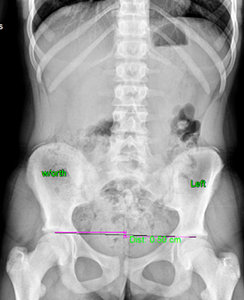

FIG 2 X-ray showing 6.8 mm femoral head height difference, higher on the right.

I then looked at her X-rays. The most important view is the A-P L-S. We took the first series barefoot. On this view, I first looked at femoral head height. She had a 6.8 mm femoral head height difference, higher on the right. (Fig. 2) On her lateral L-S view, she had a lumbarization, removing the ability to know exactly what her Ferguson's center of gravity showed, as well as her sacral base angle. On lateral cervical (Fig. 3), she had a straight cervical spine, often associated with chronic headaches. The open-mouth view (Fig. 4) showed the significant imbalance between atlas and axis.

Based on the digital laser foot scan, I ordered full-length stabilizing orthotics with three-arch support. Once the orthotics arrived, I put them in the patient's shoes and re-took the A-P L-S view to see how the orthotics affected femoral head height. The repeat X-ray of the A-P L-S showed there is now a 5.0 mm femoral head height difference, (Fig. 5), showing orthotics help reduce the difference. However, a heel lift was still needed. I applied a 5 mm heel lift to the left orthotic.

FIG 5 A-P L-S view indicating a 5.0 mm femoral head height difference following use of orthotics.